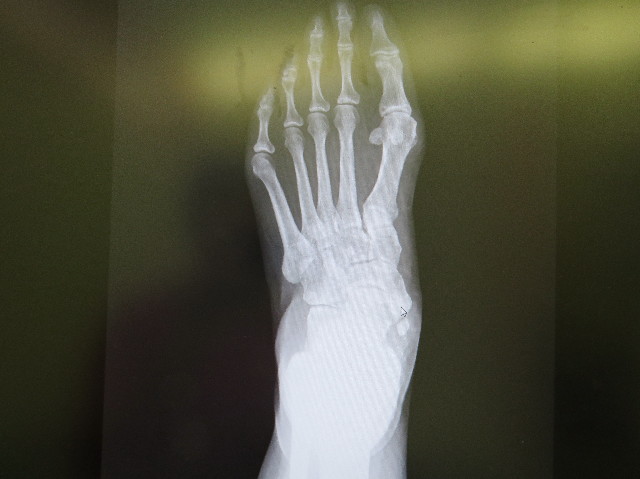

これ(下の画像)は前の先生のところで撮ったレントゲンですが

こんなに大きな『石灰化』は初めて見たと助手の先生がおっしゃっていました。

持参したMRI画像をみたところでは、外脛骨周辺だけでなく、腱やスジの炎症がかなりあって、この炎症のせいで痛いのでしょうとのこと。

(炎症部分が長く大きくあちこち真っ白に写っていてよくわかります)

画像診断(MRIの見方)も随分と違うものだと感じました。